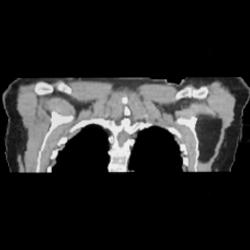

Sclerotic Bone Metastases